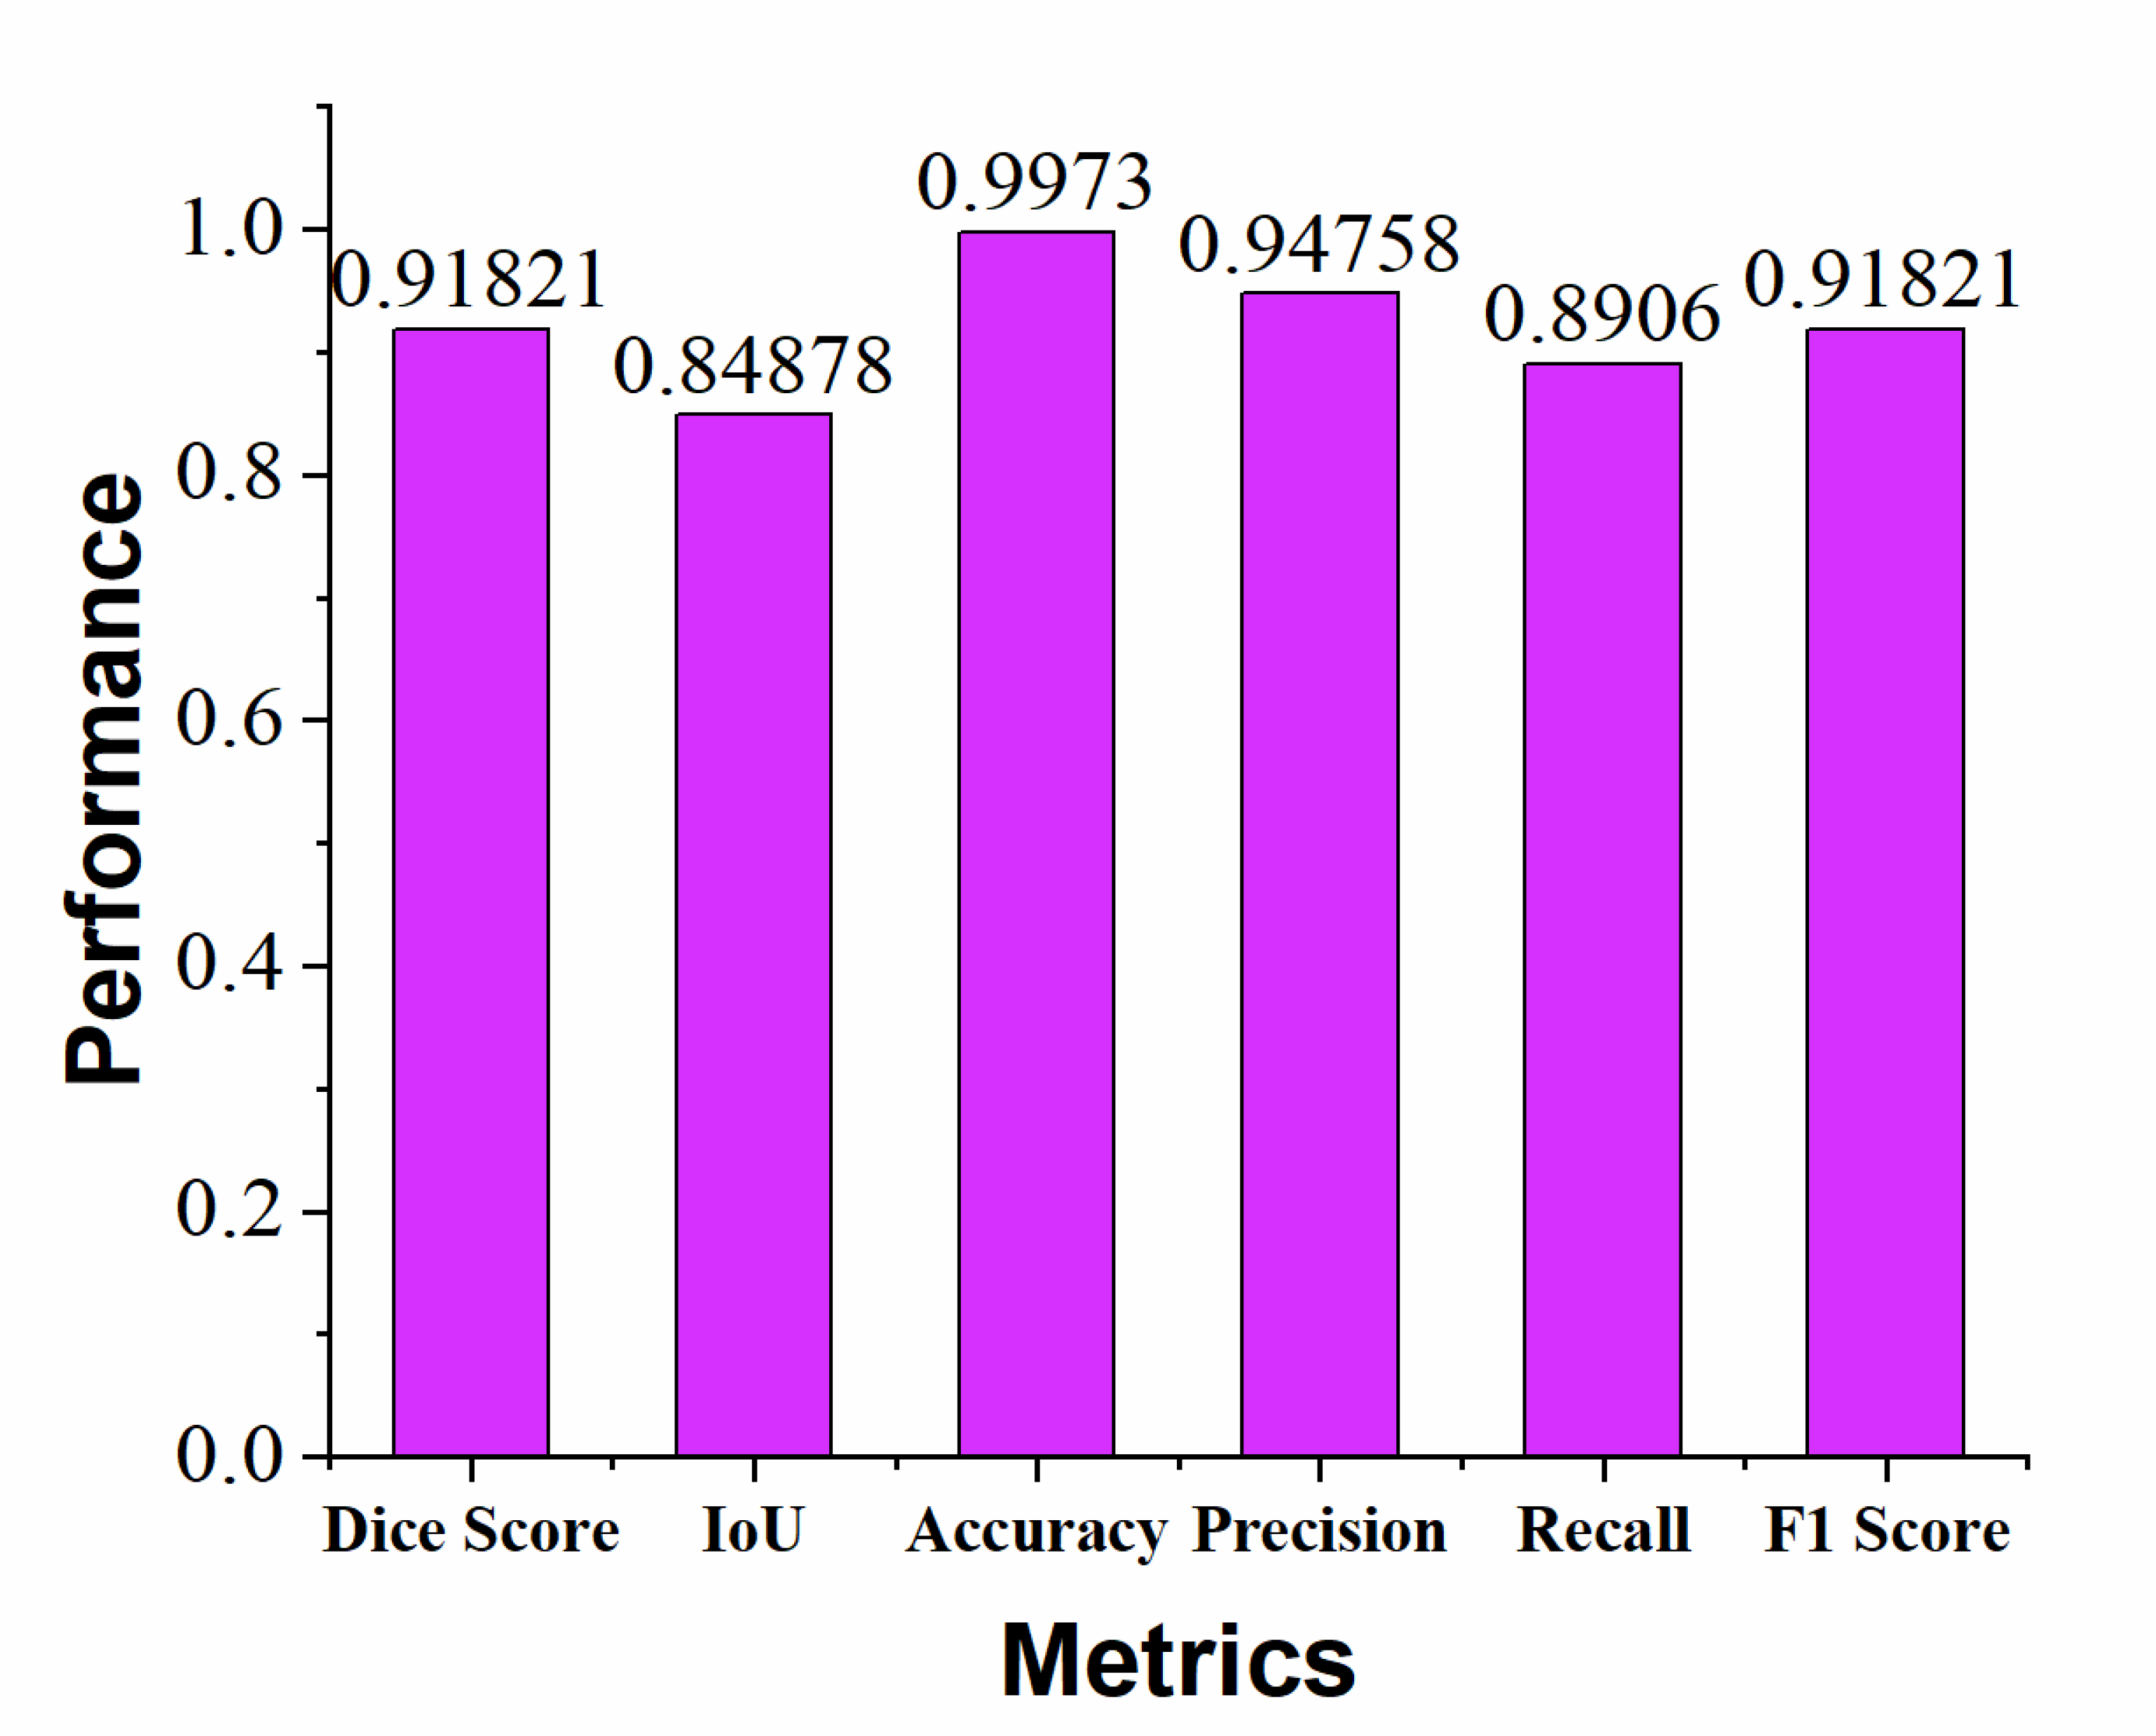

Segmentation quality was evaluated using key performance metrics, including Dice Coefficient (DSC), Intersection over Union (IoU), accuracy, recall, precision, and F1 score. The segmentation results are illustrated in Fig. (9) using these metrics. Our model achieved an accuracy of 99.73%, a recall of 89.06%, a precision of 94.75%, a DSC of 91.8%, an F1 score of 91.82%, and an IoU of 84.87%. These results demonstrate that the proposed model provides highly accurate and reliable segmentation of brain tumours.

Proposed model metrics vs. performance.